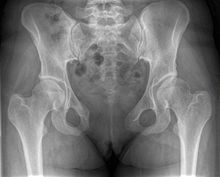

Post traumatic diastasis of symphysis pubis

X-ray

Separation of symphysis pubis (diastasis)

An X-ray film will show a marked gap between the pubic bones, normally there is a 4–5 mm gap but in pregnancy, hormonal influences cause relaxation of the connecting ligaments and the bones separate up to 9 mm. To demonstrate instability of the joint the patient is required to stand in the "flamingo" position, (standing with weight on one leg and the other bent).[2] A vertical displacement of more than 1 cm is an indicator of symphysis pubis instability.[3] A displacement of more than 2 cm usually indicates involvement of the sacroiliac joints.